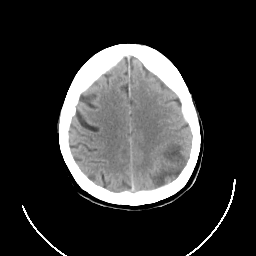

CT Study #3 -- Slice #21

[Home][Help][Clinical][Tour 1] Slice 21